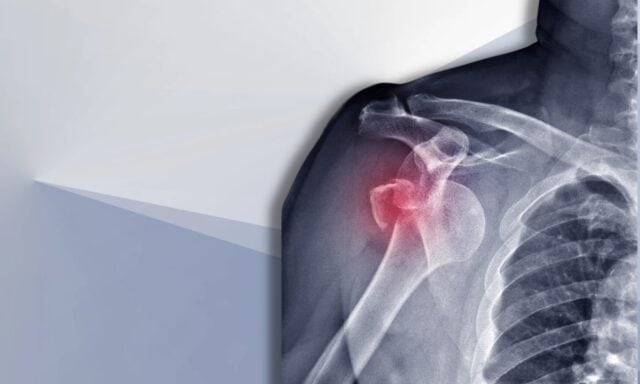

Bu bölümde omuz instabilitesi ile ilgili her şeyi konuşacağız. Stanmore sınıflandırması ve dislokasyon sonrası yapısal hasar hakkında daha fazla bilgi edineceksiniz. Omuz instabilitesi olan tipik bir hastayı ve muayene sürecinin nasıl göründüğünü tartışacağız. Kas aktivasyon paternleri, cerrahi ve omuz instabilitesi olan bir hastanın fizyoterapötik yönetiminin nasıl olabileceğine değineceğiz. Bu yüzden tüm bölümü dinlediğinizden emin olun!